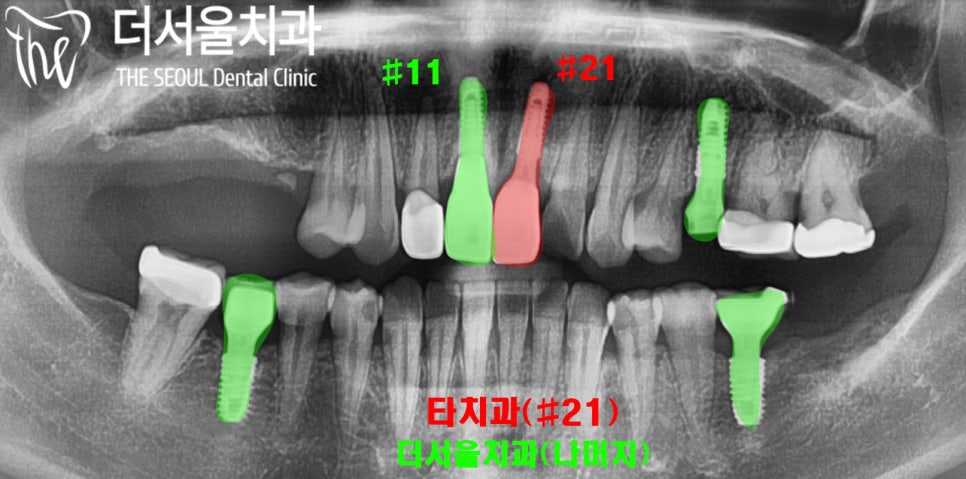

엑스레이를 촬영해 보았습니다.

#21은 2개월 전 다른 곳에서,

#11을 포함한 나머지 보철은

4년 전 저희가 해드렸습니다.

4년 전 진료 기록

저희가 해드린 보철은

이전 진료 기록과 비교하여

보니 별다른 문제 없이

잘 사용하고 계신 것을 확인했습니다.

엑스레이 사진을 보면

왼쪽이 더서울 성남 치과

오른쪽이 타원 보철인데

앞서 말씀드린 이머전시 프로파일의

차이가 있는 것이 보여집니다.

다른 곳에서 하신 임플란트와 크라운의

연결 지대주에 문제가 있는 것 같습니다.

굴곡진 부분이 보이시나요?

11번 치아는 매끄러운

라인으로 이어지는 반면에

21번은 풍융도가 큰 라인으로

이어지고 있습니다.

이곳이 부드럽게 이어지지 않아

잇몸에 염증이 생겨

발적과 부종이 있습니다.